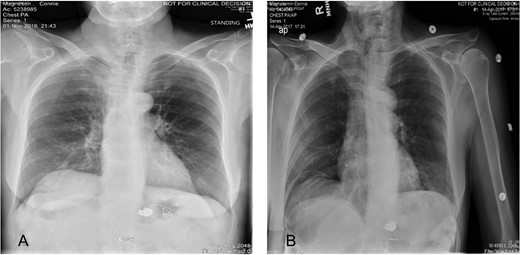

A 65 -year-old woman with a known history of multiple splenic and hepatic aneurysms was admitted to our hospital in October 2012 with acute abdomen. Abdominal computed tomography angiography showed rupture of splenic aneurysm with active extravasation of contrast and associated large left upper quadrant hematoma with small hemoperitoneum (Fig. 1). Visceral angiogram confirmed the presence of three fusiform aneurysms involving midsplenic artery (Fig. 2). The distal most aneurysm demonstrated large extravasation (Fig. 3). Coil embolization of the proximal and midsplenic artery aneurysm was performed using multiple Nester coils (Cook Medical, USA) with cessation of antegrade flow (Fig. 4). Attempt to access distal portion of the splenic artery was unsuccessful. She recovered well and was discharged 4 days later. In December 2016, she was admitted with dyspepsia and severe iron deficiency anemia requiring blood transfusion. A colonoscopy and upper endoscopy were performed which showed the presence of metallic coils in the stomach (Fig. 5). The patient subsequently underwent a combined upper endoscopy and laparoscopy. Three 5 mm ports were used to expose the lesser sac in event of hemorrhage during extraction of the coil endoscopically. An atraumatic bowel clamp was placed distal to the Treitz ligament to prevent insufflation of the small bowel. Upper endoscopy was performed using CO2 insufflation and the Nester coils were retrieved using rat tooth forceps (Fig. 6). There was no bleeding in the lesser sac after removal of the coils. A leak test was performed to rule out gastric perforation. She had an uneventful recovery and was discharged the next day.

(A) Plain abdominal radiograph comparing preoperative migrated coil into the stomach. (B) Postoperative film showing coil successfully retrieved.